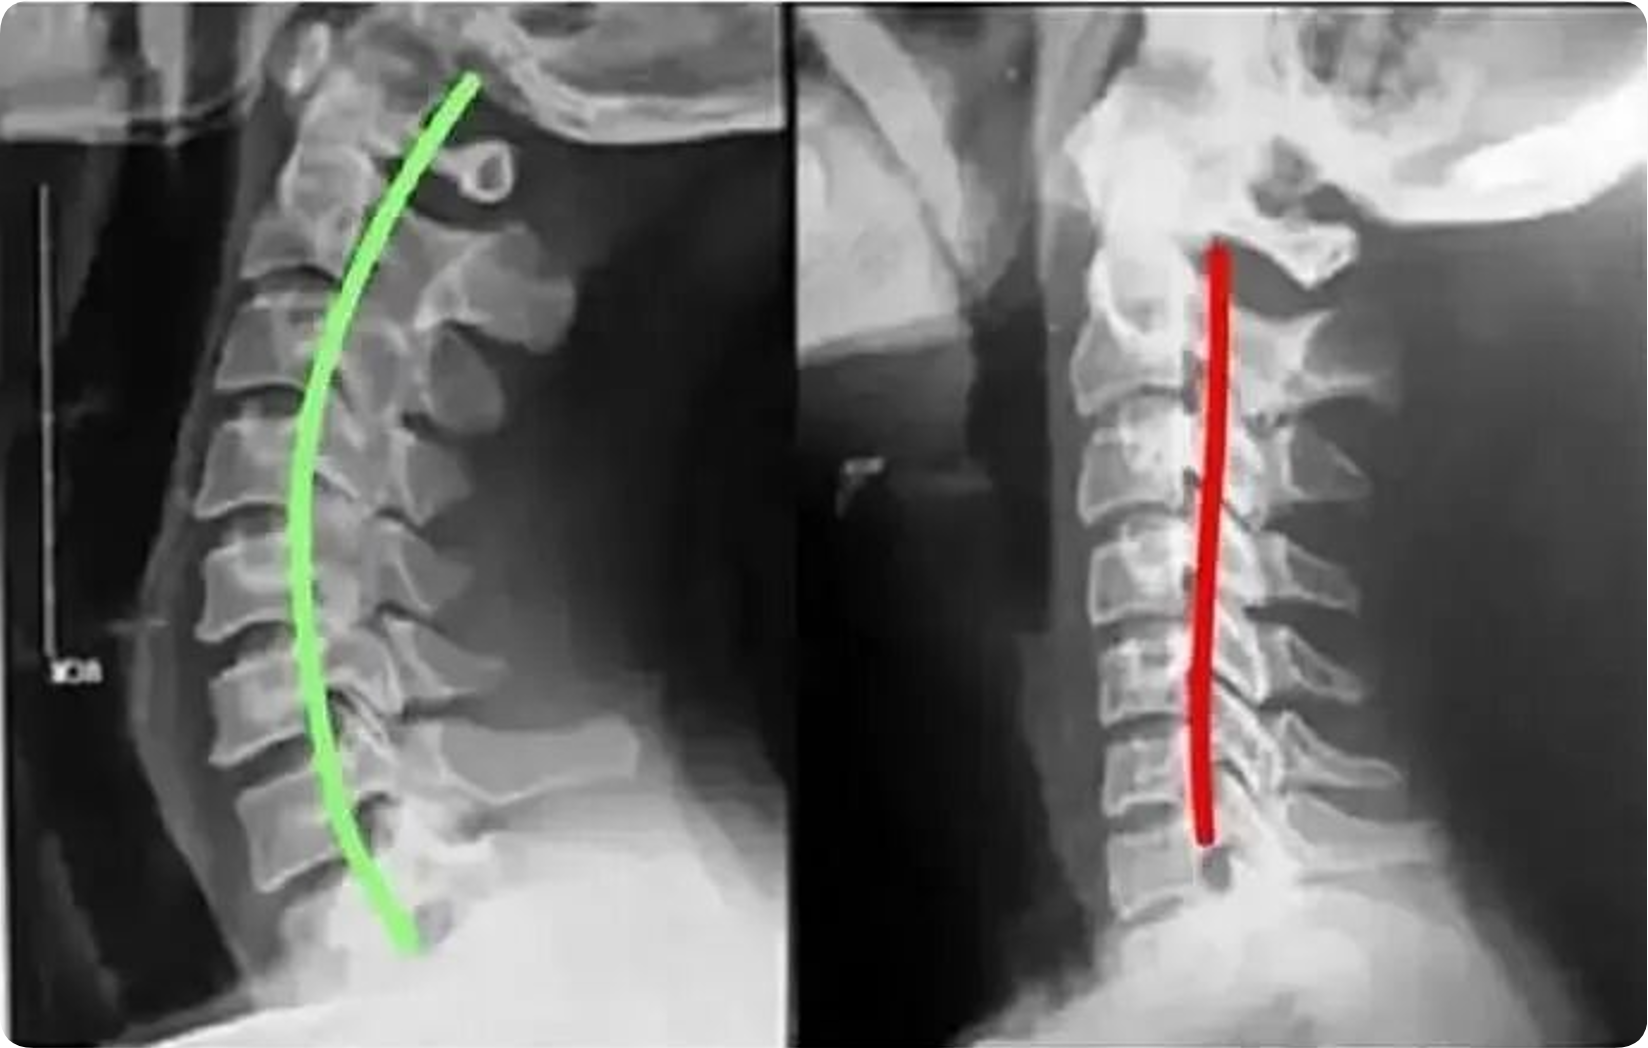

患者均有上颈段不适、头前屈后伸及颈部左右旋转受限,查体上颈段棘突有偏歪,局部压痛明显。颈椎X线检查:颈椎前后缘有骨 质增生,椎间隙变窄,生理曲度变直或颈 椎后缘连线中断、反弓;后纵韧带钙化,双线征、双突影,椎体呈仰、俯式或旋转式移 位;张口位示寰齿侧间隙及寰枢关节间隙左右不对称,寰枢椎外侧缘左右不对称, 齿状突轴线至枢椎外侧缘距离不相等,或 与寰椎的中轴线不重叠,二轴线互成夹角或分离。

手法整复,纠正了偏歪的 棘突,使错位的椎体复位,解除了对颈总 静脉、颈内动脉、迷走神经及颈前交感神 经节的压迫,解除了脑干神经核供血不 足,也解决了局部面神经供血不足,从而 达到治疗面瘫的目的;手法整复,还调整 了错位的小关节,松解了椎体周围挛缩的 肌肉韧带,消除或改善了椎体失衡状态, 恢复了颈椎力学平衡,改善了局部软组织 对血管神经的压迫,改善了局部血液循 环,有利于面瘫的回复。